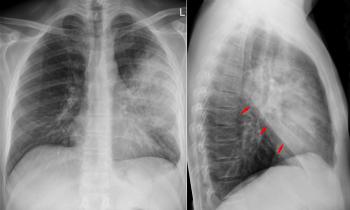

После первичного осмотра, в ходе которого врач должен осмотреть грудь и кожные покровы пациента, проверить на увеличение лимфатические узлы, послушать ритм сердца, назначаются лабораторные исследования. В первую очередь больного направляют на рентгенографию легких, затем у него берут кровь. В некоторых случаях прибегают к бактериологическому посеву мокроты, ПЦР-диагностике, к радиоиммунному анализу. Для обнаружения атипичный микроорганизмов и коронавируса используют серологическую и полимеразную цепную реакцию.